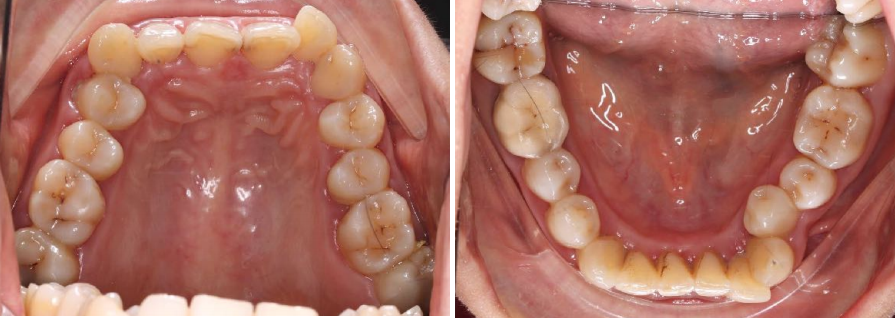

这位女士主诉牙不齐、咬合深,想要通过牙齿矫正改善牙齿问题和协调面型。

通过牙片资料可以看到女士是闭锁性深覆合,上牙几乎把下牙完全盖住,整个咬合关系并不是很理想,从侧貌看,她的下嘴唇相对靠后,下巴有点后缩,颏唇沟很深。